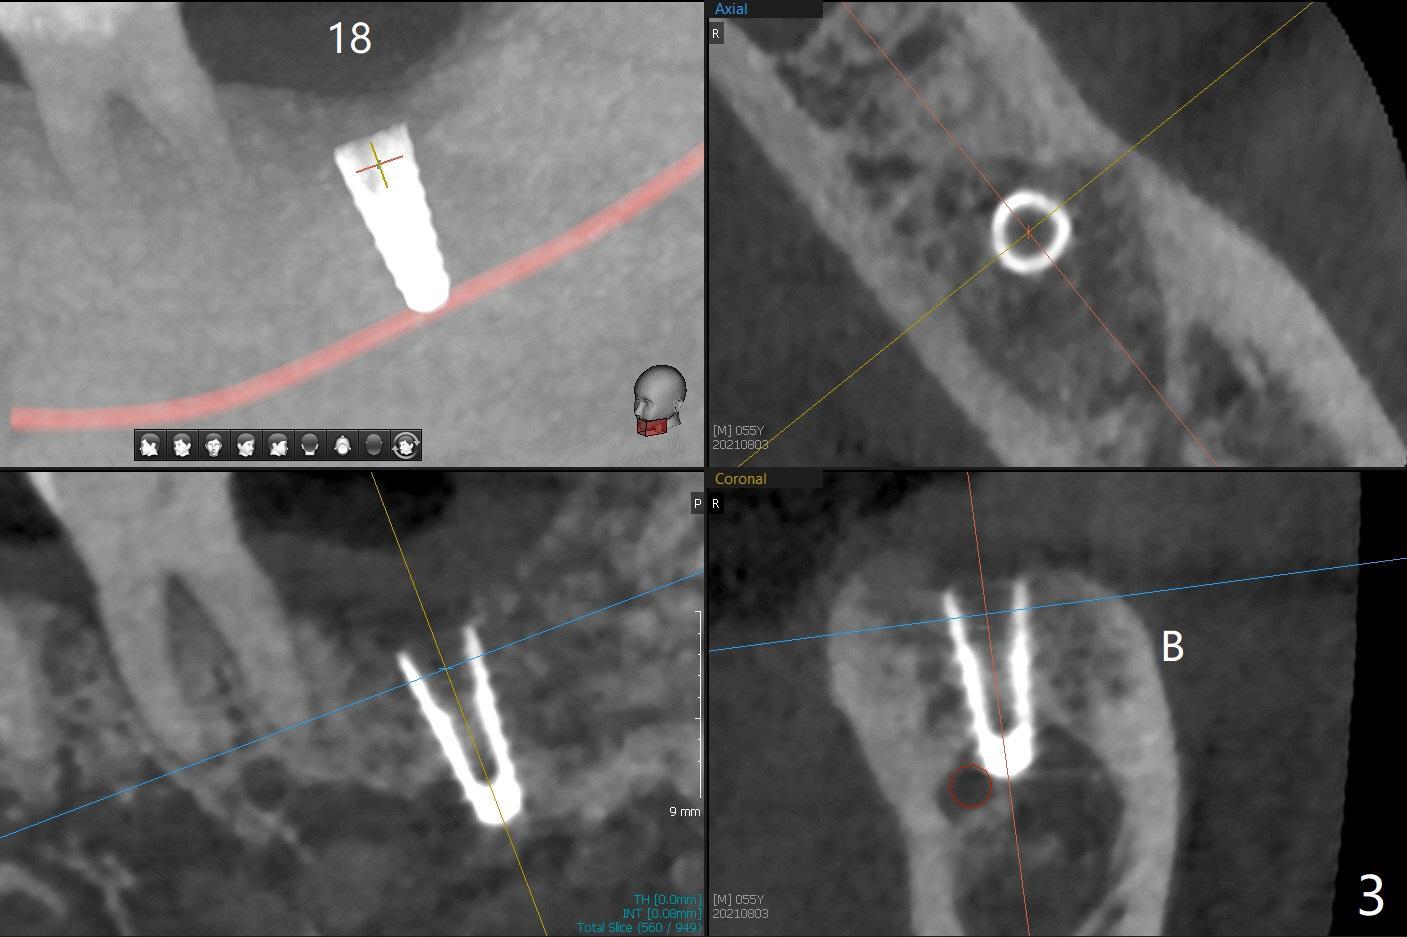

导板种植是否需要切开取决于牙槽嵴角化龈宽度,放置导板后,插入环形刀(图一),用手的压力(不要开手机)接触牙龈后,抽出环形刀,并且取出导板,检查环形标记是否累及颊侧粘膜(图二)。这个病例没有,所以没有切开,也没有保留角化龈(骨质硬,预计术后可以使用愈合基台)。在34毫克利多卡因17微克肾上腺素浸润(jinrun)麻醉下,完成钻洞(最后钻头3.5x10毫米),植体植入,拍摄CT却发现植体非常接近神经(图三,五),似乎钻洞向舌侧偏移(与设计(图四)对比),可能与没有远中牙齿固位有关。由于术中没有疼痛,估计没有直接损伤神经,放置愈合基台,在后者周围空间塞入骨粉(图六:*)。理想情景使用2.2x7.3毫米钻头后,拍摄CT,最后植入4.5或者5.0x7.3毫米植体(图五')。术后没有疼痛也没有麻木。